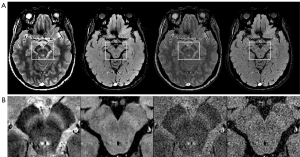

A commercial DLR algorithm (AIRTM Recon DL, GE Healthcare) was embedded in the MR data reconstruction pipeline, producing an appropriate trade-off between the signal-to-noise ratio, spatial resolution, and scanning time (44,45). It comprised a deep convolutional neural network that uses raw complex-valued imaging data to reconstruct images with a high signal-to-noise ratio, reduced truncation artifacts, and high spatial resolution (43,45). The convolutional neural network was trained using a supervised learning approach with over 4.4 million parameters in more than 10,000 kernels. Each acquisition simultaneously had two sets of images from a single set of raw k-space data obtained during scanning. Notably, one set of images was reconstructed using DLR, and the other using conventional reconstruction was defined as NON-DLR (no applied DLR). This study applied the DLR on NM-MRI based on GRE with and without an MT pre-pulse. The representative images are shown in Figure 2 (the DLR NM-MRI with and without pre-pulse and the NON-DLR NM-MRI with and without pre-pulse from left to right in Figure 2A; the magnified views of the white boxes corresponding to Figure 2A in Figure 2B).